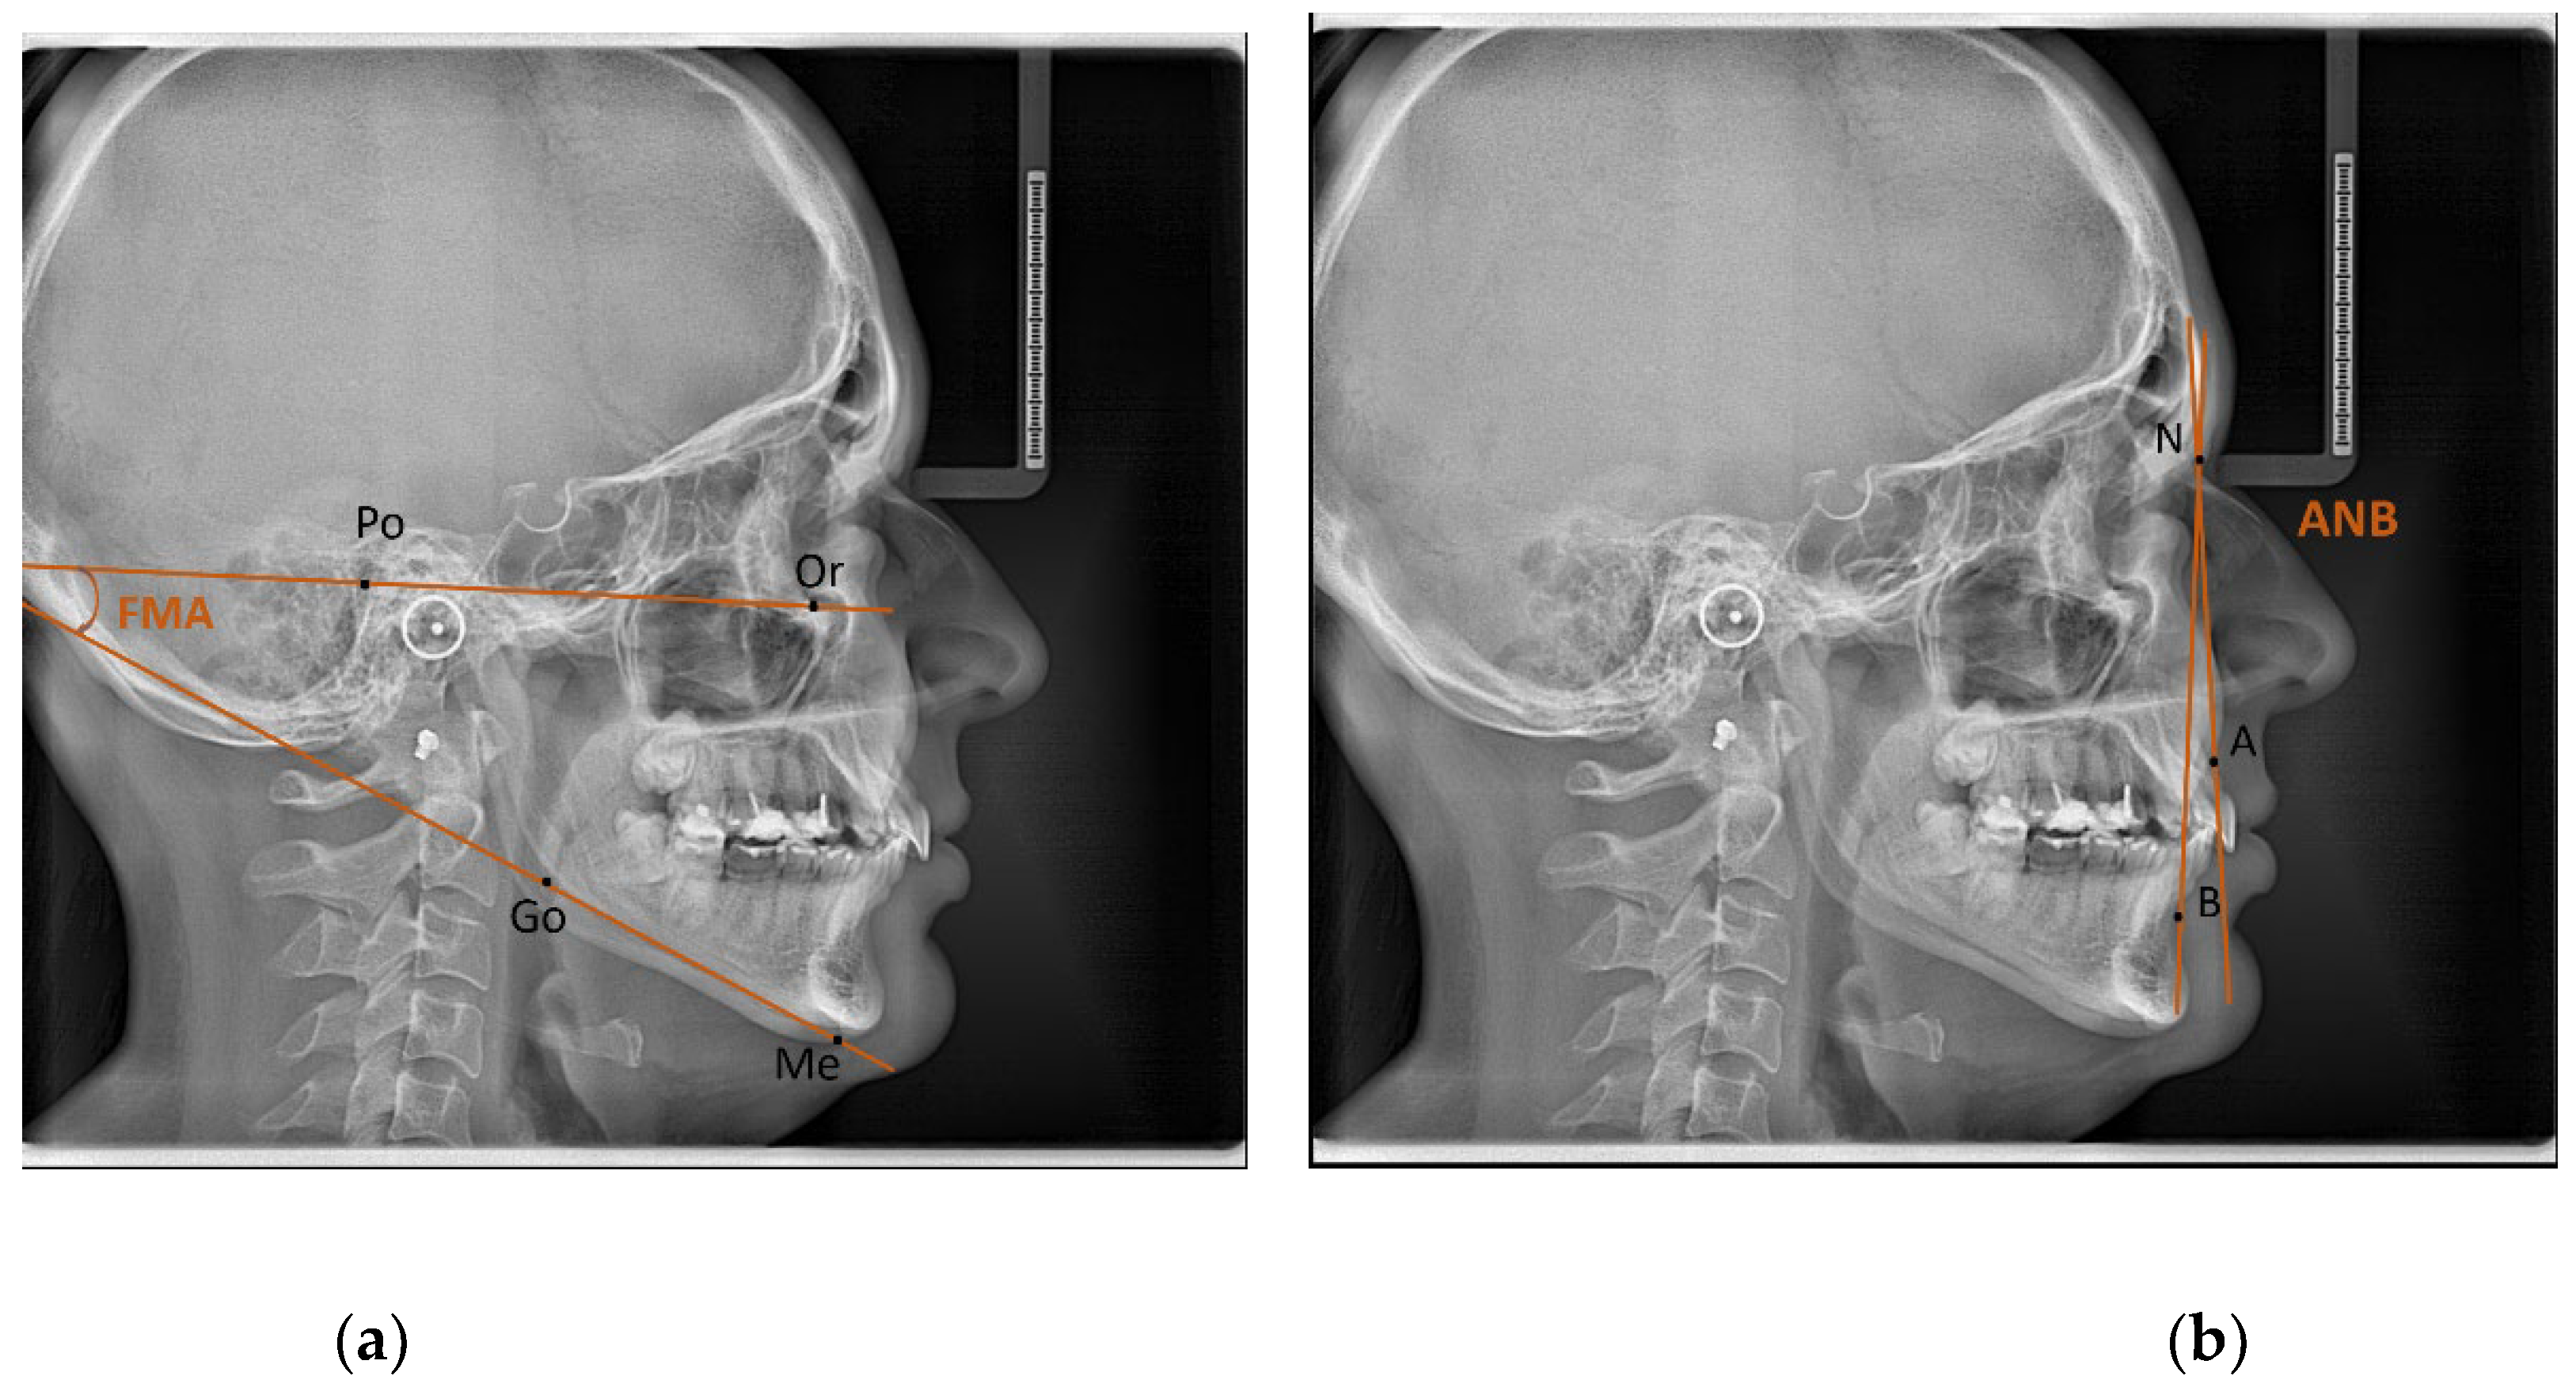

| 1 | ANB (°) | Angle between the Nasion-A point and the Nasion-B point plane [19]. |

| 2 | FMA (°) | Angle formed by the FH plane and the mandibular plane [19]. |

| 3 | GONIAL ANGLE (°) | At lateral cephalograms, it was determined at the junction of the mandibular and ramus planes. A line tangent to the lower border of the mandible and another line tangent to the distal border of the ascending ramus and the condyle on either side were drawn in order to measure the gonial angle in the panoramic radiographs [20]. The mandibular plane and the ramus plane’s built point of junction. |